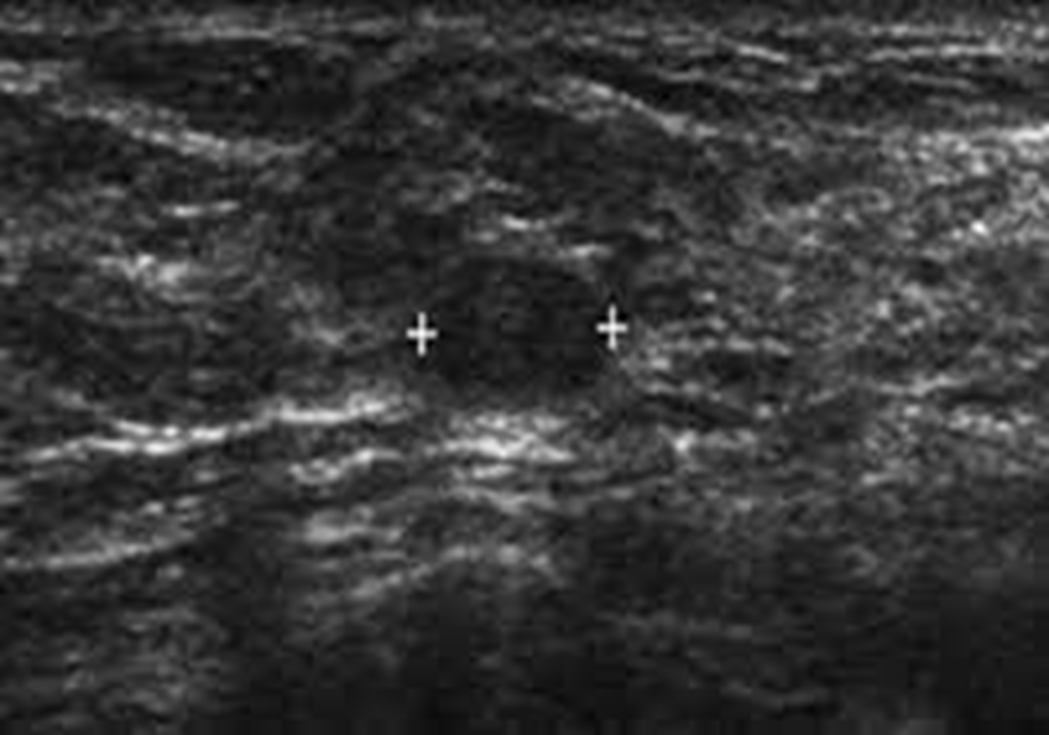

What is this image showing?

LCIS